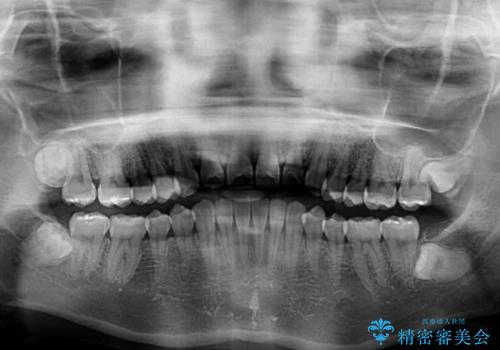

話しにくいオープンバイト インビザラインによる矯正治療

- 前歯の上下スペースによる話しにくさを気にして来院された患者様です。

インビザラインにより上下の前歯の隙間を閉じていくこととしました。

上下の奥歯を圧下させるようにすることで、前歯を接触させるように計画しました。

隙間に舌が入り込むことが話しにくさに繋がっていたため、舌の筋肉のトレーニングも並行して行い、話しにくさの改善と後戻りの抑制を図りました。